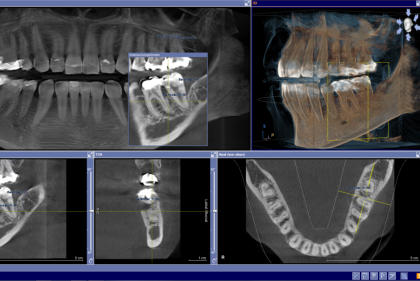

Panorama und DVT - 3D -Volumentomographie

Für den Zahnarzt haben Röntgenaufnahmen einen unverzichtbaren Stellenwert in der Diagnostik und Behandlungsplanung. Für die Implantologie und viele andere zahnärztliche Bereiche bietet das digitale Röntgen eine optimale Möglichkeit der Vorplanung und Unterstützung während der Behandlung. Digitale 2D-Röntgenbilder und DVT´s/ 3D-Röntgenbilder können wir in besonders hoher digitaler Qualität und geringer Strahlendosis durchführen.

sehr hohe Auflösung und Kontrast sehr geringe Strahlenbelastung sofortige Bilddarstellung in Echtzeit optimale Vergrößerungsmöglichkeiten umfangreiche Bildnachbearbeitung punktgenaue Vermessung von Strecken gemeinsame Ergebnisauswertung mit dem Patienten Hochauflösende Panoramaaufnahme:

Anwendungsgebiete für die 3D-Diagnostik in unserer

Zahnarztpraxis Celle sind:

Implantologie Endodontie spezielle Parodontologie Chirurgie Zahnersatz Kieferorthopädie